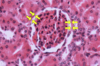

Kupffer cells - system of macrophages, known as Kupffer cells (KC), are found interspersed among the endothelial lining cells of Liver sinusoids (Si). these macrophages are larger than the epithelial cells and may be recognized by the presence of phagocytosed material within them. Kupffer cells may be demonstrated by injecting an animal intravenously with indian ink, as in this specimen. Some cells appear as large black smudges because they are filled with phagocytosed ink (arrows), whereas other cells possess only small quantities of the phagocytosed material (arrow heads). Note that much of the sinusoidal lining devoid of ink, indicating that the endothelial cells are probably not phagocytic.